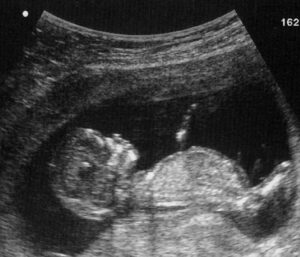

This case is especially alarming because the woman was admitted to the hospital where they had all of the technology to monitor her and her baby. She demonstrated high blood pressure which automatically put her at a higher risk for placental abruption. Even so, doctors and nurses chose not to monitor the fetal heart rate until she had already been in the hospital for five days. Doctors could have done an ultrasound that would presumably have shown if there had been placental abruption.